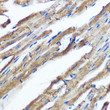

Short DescriptionRabbit monoclonal IKK Epsilon (1-100) antibody for use in WB, IHC-P and ELISA in human, mouse and rat samples. Datasheet included with dilution recommendations, and related reagents.

ApplicationsWB/IHC-P/ELISA

ReactivityHuman/Mouse/Rat

IHC-P:1:50-1:200